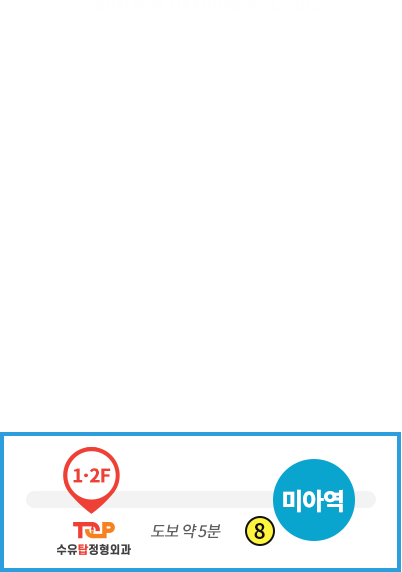

비수술 치료부터 고난이도 수술까지!

수술을 잘하는 의사가 비수술 치료도 잘합니다.

- 고난이도 척추 수술 및 시술 20,000여회 집도

- 척추신경주사 및 관절주사 40,000여회 시행